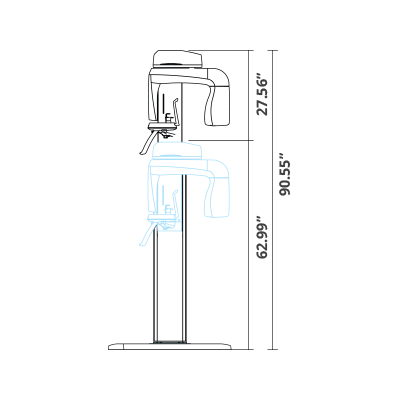

| TYPE | TOP VIEW | FRONT VIEW |

|---|---|---|

|

PaX-i (Pano) |

|

|